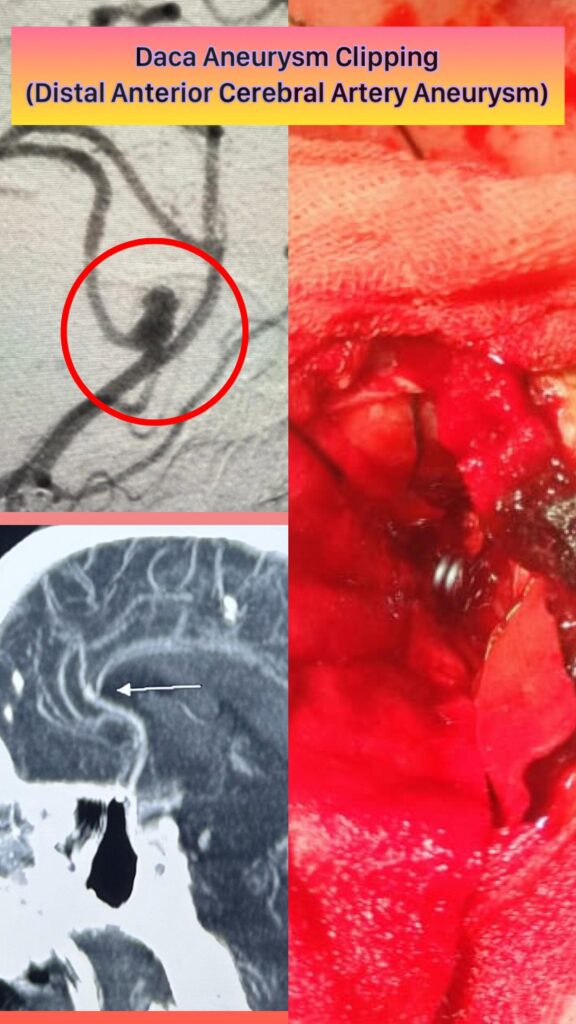

Dr. Ridham Khanderia, MBBS, MS (General Surgery), MCh (Neurosurgery) is a Neuro and Spine Surgeon with over 4 years of clinical experience and more than 2,000 neurosurgical and spine procedures performed. He completed his MBBS from PDU Medical College, MS in General Surgery from MP Shah Medical College, and MCh in Neurosurgery from AIIMS Rishikesh. He also holds a Fellowship in Endoscopic Spine Surgery from Pune.

He specializes in back pain, slip disc, sciatica, and complex spine and brain disorders, with a strong focus on conservative treatment, minimally invasive surgery, and ethical, patient-centered care.